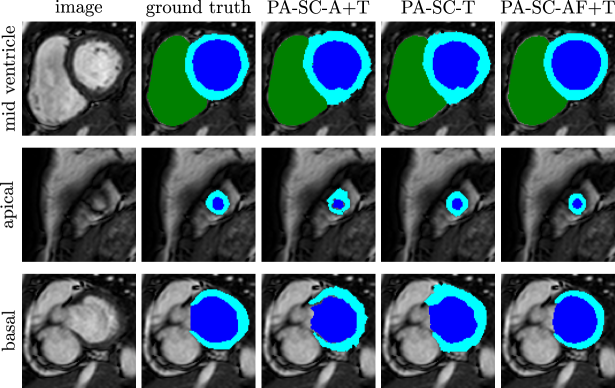

Finally, we examined the performance of our framework when using data annotated with scribbles as proposed in Sec. 3.2. In a first group of experiments, we investigated the scenario when the scribbles were available only on the atlas images. This partial annotation scenario will be referred to as PA-SC-A and was compared against MASr-LW with fully annotated atlases as a gold standard. We used the graph configuration CONF1 (as shown in Fig. 6(a)) since manual labels were available in roughly the same locations in all images (as opposed to the slicewise annotation strategy where entire slices remained unlabelled). Therefore, the complex propagation scheme CONF2 was not deemed necessary. In the second group of experiments, we examined scenarios which involve placing scribbles on a target image before automated segmentation, closely related to [28]. In the simplest configuration, scribbled were placed solely on the target image (PA-SC-T) [28], and no atlases were used. We then investigated if, in addition, a “scribbled” atlas database would improve these results (PA-SC-A+T). Here, scribbles were available both in the atlas database and the target image. Lastly, we used fully annotated atlases in combination with a scribbled target image (PA-SC-AF+T) to obtain a target segmentation with the proposed framework.

Figure 12(a) shows mean Dice coefficients for the first group of experiments, where scribbles were placed on the atlases, and completely unlabelled target images were segmented using the proposed framework. It can be seen that using scribbled atlases (PA-SC-A) yielded results comparable to MASr-LW (where fully annotated atlases were used) for the right and left ventricle. For the myocardium, using scribbled atlases could not match the accuracy achieved when using fully annotated atlases. Figure 13 shows example segmentation results for one subject. It can be seen that the results of PA-SC-A and MASr-LW are similar. However, since there is no boundary delineation in the scribbled atlases, the resulting segmentation results for PA-SC-A were more intensity driven as can be seen for example in the myocardium in the mid-ventricular view.

The results for the second group of experiments are shown in Fig. 12(b). Here, the target images to be segmented contained scribbles. In the simplest configuration PA-SC-T, a target segmentation is obtained from the scribbled target image only. Adding the scribbled atlases (PA-SC-A+T) yielded results very similar to PA-SC-T. However, placing scribbles in a target image to aid segmentation using fully annotated atlases (PA-SC-AF+T) yielded considerable improvements over both PA-SC-T (as seen in Fig. 12(b)) and MASr-LW (as seen in Fig. 12(a). Visual results for these experiments are shown in Fig. 14 for the same subject as above. It can be seen that all three methods containing target scribbles were able to detect the myocardium in the apical slice, which was not possible using only atlas information (as seen in the middle row in Fig. 13). Furthermore, it can be seen that the segmentation obtained with fully annotated atlases and a scribbled target image (PA-SC-AF+T) is visually very similar to the ground truth segmentation, which is also reflected in the high Dice scores reported in Fig. 12(b).